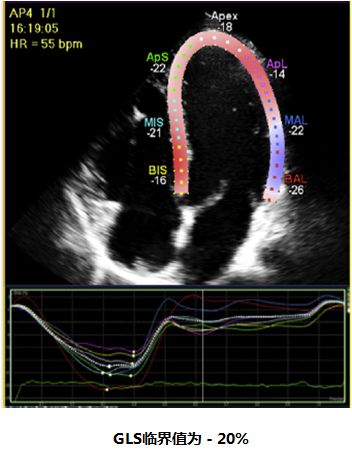

➤ 2.3 左室整体收缩功能——整体长轴应变(GLS)

1、无角度依赖性;

2、预后价值明确;

3、整体GLS为三个切面平均值;

4、数据分析与生产商有关;

5、受图像质量、帧频及心尖缩短影响。